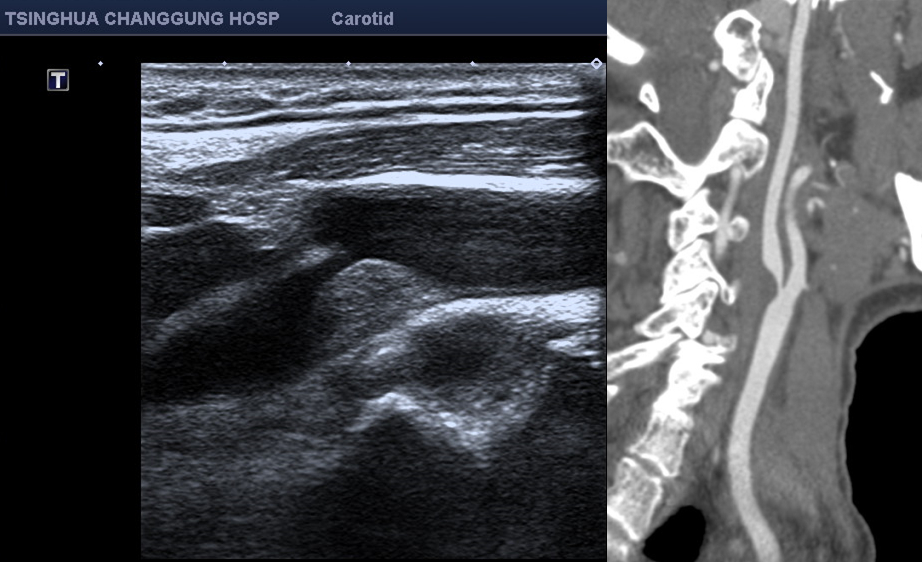

患者乔大爷今年63岁,元旦时突然出现右眼视力模糊,数分钟后恢复,同时还出现了头晕等症状。乔大爷赶忙来到北京清华长庚医院就诊,血管外科副主任医师张童接诊后,立即为患者安排了超声及CTA(CT血管造影)检查,检查结果明确提示患者为右侧颈动脉重度狭窄。

术前影像学检查